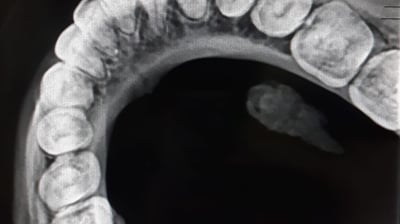

Radiografii occlusale

Radiografiile occlusale sunt utile pentru a evalua relația dintre dinți în timpul mușcării și pentru a depista probleme legate de alinierea dinților